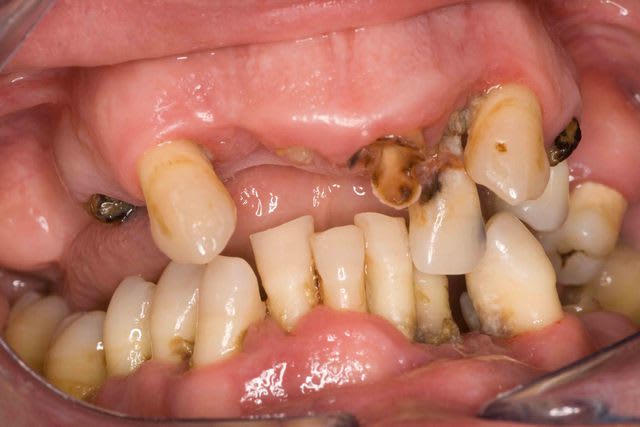

chicot29

Modeste contribution, rebasage au tartre.... Mais on peut faire mieux je n'ai pas détecté de vers à l'intérieur !